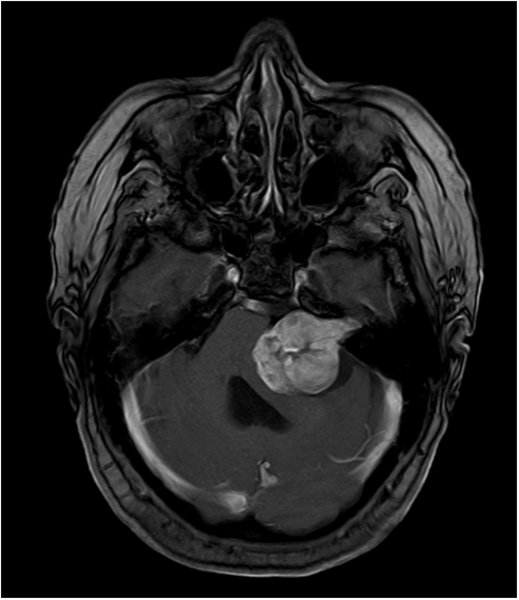

Akustikusneurinom T1 mit KM - axial

Akustikusneurinom mit typischem "Eistüten"-Bild.